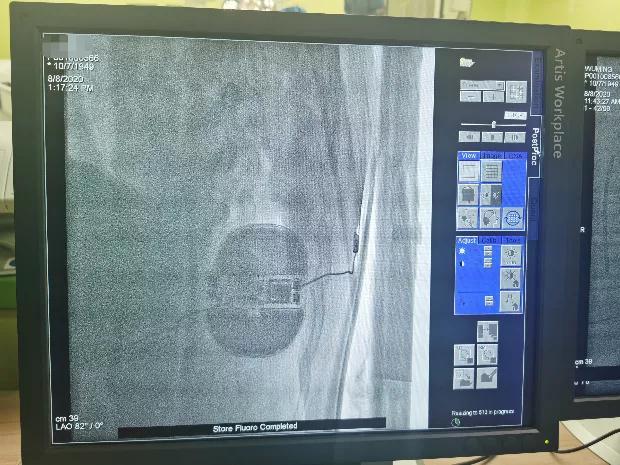

于剑突下切开皮肤2cm,逐层分离皮下组织至筋膜层,通过隧道穿引针连接囊袋,再沿胸骨向上约14cm处切开皮肤1cm,逐层分离皮下组织至筋膜层,通过隧道穿引针连接剑突下切口,使用隧道穿引针将45cm长的3501除颤电极从囊袋经隧道送至剑突下切口,固定电极中段,再使用隧道穿引针将电极经隧道送至胸骨上方切口,固定头端。连接脉冲发生器A209,置入囊袋内,逐层缝合筋膜层及皮下组织,进行DFT测试,采用50HZ,200MA交流电方式进行诱颤,SICD正确识别,经首次65J除颤成功,除颤阻抗58欧姆。缝合皮肤 ,术区纱布覆盖,包扎,弹力绷带加压包扎止血。手术圆满成功,耗时约1小时。